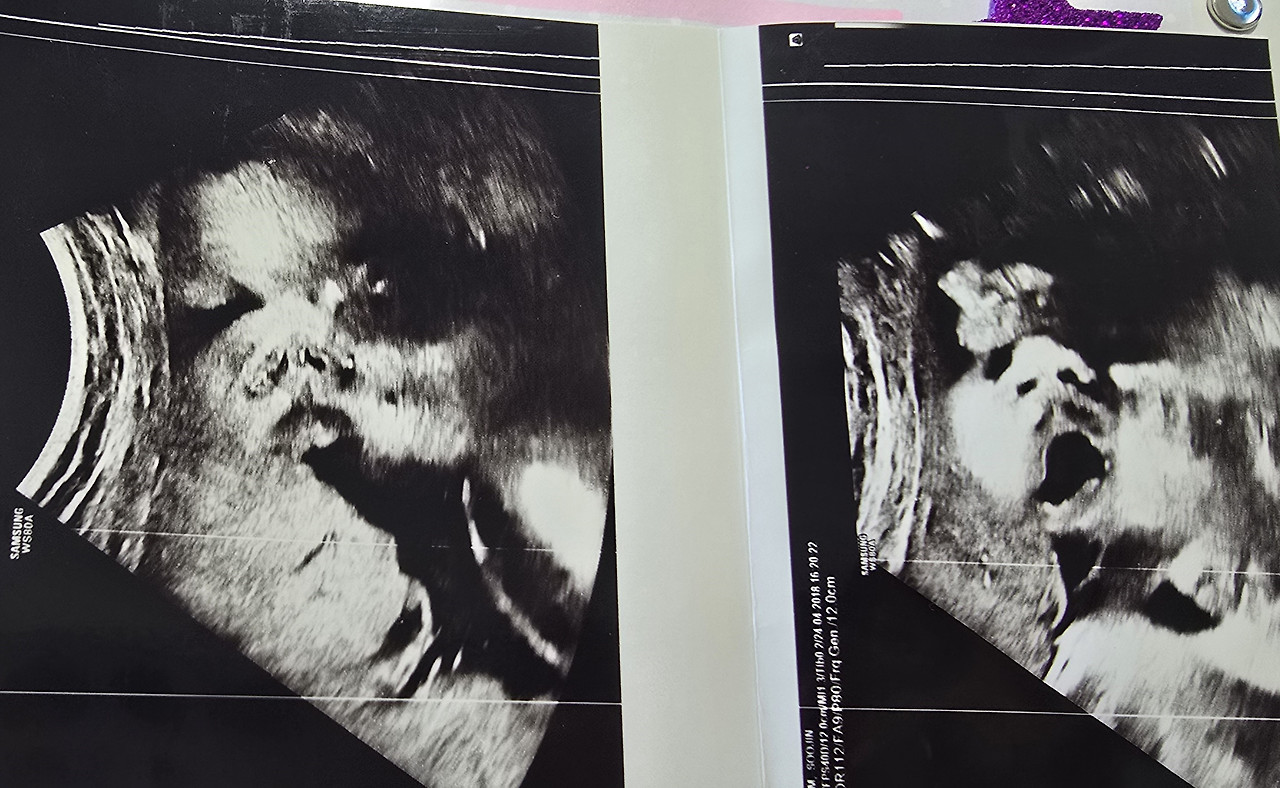

초음파를 보러 갔는데, 우리 알콩이 태어나기 전부터

어떻게 생겼는지 대략 윤곽이 나타나서 엄마랑 아빠는 하루 종일

"코가 오뚝하네, 입술은 도톰한가? 이건 볼살인가 봐. 어떻게 너무 귀여워!"

"이건 하품하고 있는 건가? 빨리 보고 싶다!!" 하며

난리부르스를 떨었던 기억이 생생해.